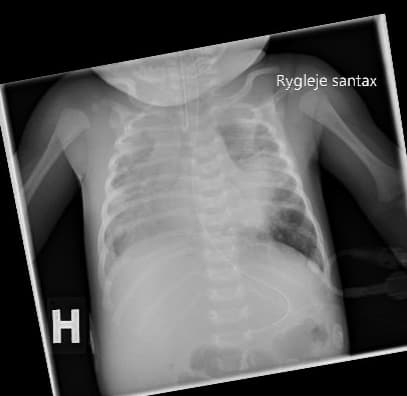

En tre uger gammel pige blev indlagt på et lokalsygehus efter et døgn med hoste, respirationsbesvær og cyanosetilfælde. Hun blev lagt i nasal continuous positive airway pressure (n-CPAP). En røntgenundersøgelse af thorax viste bilaterale infiltrater, og der blev påbegyndt behandling mod pneumoni. I en svælgpodning fandt man dagen efter B. pertussis-DNA ved polymerasekædereaktion (PCR), og der blev påbegyndt behandling med clarithromycin. Trods antibiotikabehandling og respirationsstøtte i form af n-CPAP måtte pigen overflyttes til et neonatalt intensivafsnit i respirator.

Røntgenbillede af thorax taget et døgn inden udskiftnings­transfusion. Der ses infiltrative og atelektatiske forandringer i begge lunger samt små væskeansamlinger i begge pleurae.